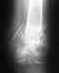

Можно ли что-то сделать, зависит от того, чем конкретно обусловлено ограничение подвижности. Возможно, так или иначе нарушена форма суставных поверхностей, или имеются оссификаты вокруг, или укорочены мышцы, или..., или..., или...

Покажите для начала свежие рентгенограммы (фас и профиль) локтевых суставов.